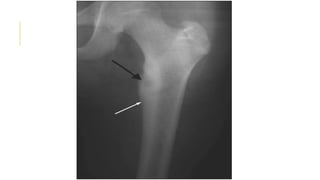

OSTEOID OSTEOMA

Presents during the second decade.

Proximal femur and tebia is the most common site.

Progressively increasing pain that is worse at night and unrelated to

activity .Pain sometime relieved by aspirin or other NSAIDs, usually

within 20 to 25 minutes

25 percent of osteoid osteomas are not obvious on plain radiographs

 X-ray show Small, round lucency (nidus) with a sclerotic margin

DDX: Stress fracture , Bone infections

OSTEOID OSTEOMA Presents duringthe second decade. Proximal femur and tebia is the most common site. Progressively increasing pain that is worse at night and unrelated to activity .Pain sometime relieved by aspirin or other NSAIDs, usually within 20 to 25 minutes 25 percent of osteoid osteomas are not obvious on plain radiographs  X-ray show Small, round lucency (nidus) with a sclerotic margin DDX: Stress fracture , Bone infections TX: Asymptomatic Observed with serial examinations and radiographs every four to six months  Symptomatic Radiofrequency ablation or Surgical resection Treatment